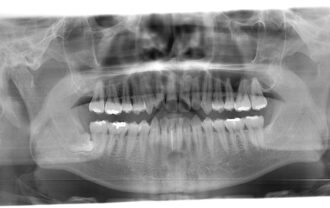

「虫歯を放置する危険性|学校医が伝える歯と健康の関係」

2025.11.28

詳細を見る虫歯を放置するとどうなるの? 学校で校医をしていると、「虫歯って放っておいても大丈夫?」「部活・受験が忙しくて・・・」という質問をよく受けます。 結論から言うと、虫歯は…